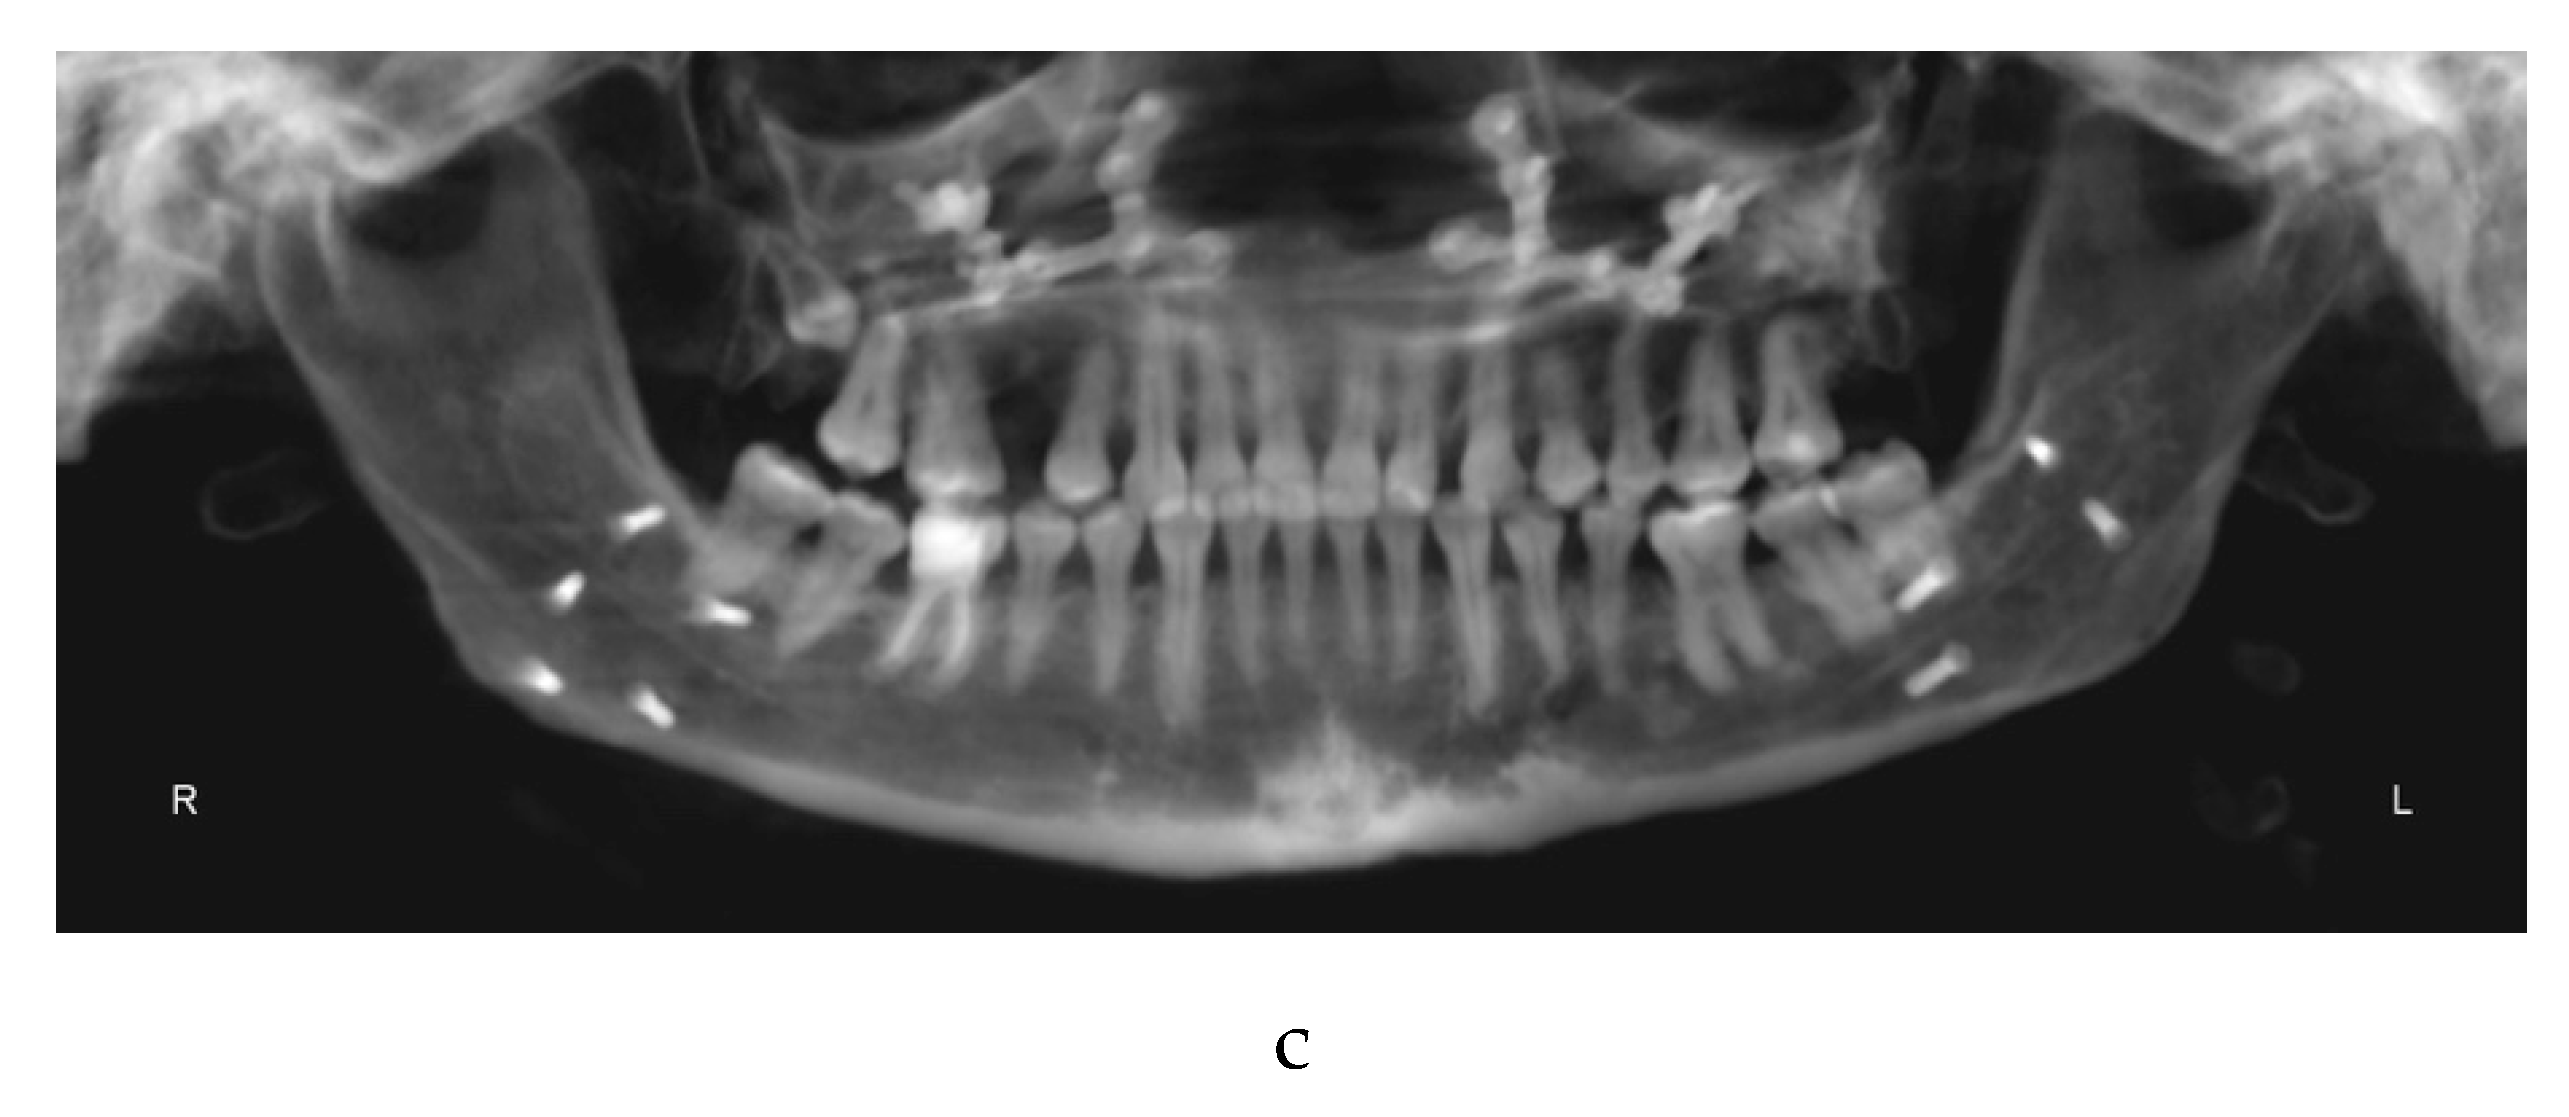

In June 2019, the objectives of the pre-surgical orthodontic treatment were considerably achieved: the arches were leveled, the teeth aligned, and the dental compensations of the third skeletal class had been removed. The pre-surgical diagnostic records were sent (Figure 2a–d) to the maxillofacial equip. Kobayashi ligatures were placed all over the teeth to prepare the patient for surgery.

In October 2019 the patient underwent maxillofacial surgery to correct the severe skeletal malocclusion and relocate the bone bases in the right relationship. The combined surgery involved maxillary Le Fort I osteotomy [29]and mandibular reduction [30]. Skeletal fixation plates were then used to stabilize the bone segments [31].

One week later the post-surgical orthodontic treatment phase started (Figure 3a–c).

Figure 2. a: antero-posterior projection of the CBCT. b: lateral-lateral projection of the CBCT. c: panoramic projection of the CBCT. d: frontal intraoral photograph. Kobayashi ligatures have been placed.